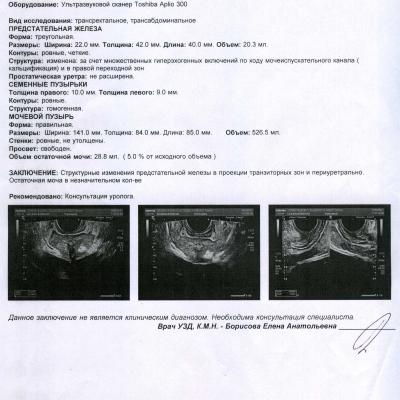

НА ДНЯХ СДЕЛАЛ УЗИ МОШОНКИ И ПРОСТАТЫ, ТАК ВОТ ПО ЯИЧКАМ ТИПА ВСЕ НОРМ А ВОТ В ПРОСТАТЕ ФИБРОЗНЫЕ ИЗМЕНЕНИЯ ПОХОДУ МОЧЕИСПУСКАТЕЛЬНОГО КАНАЛА И В ПРАВОЙ ДОЛЕ.

МОЖЕТ ЛИ ФИБРОЗ ДАВАТЬ БОЛИ В ЯИЧКА? И ЧТО ДНЛАТЬ С ТАКИМ ФИБРОЗОМ? ФОТО АНАЛИЗОВ ПРИЛАГАЮ. По крови повышены лимфоциты